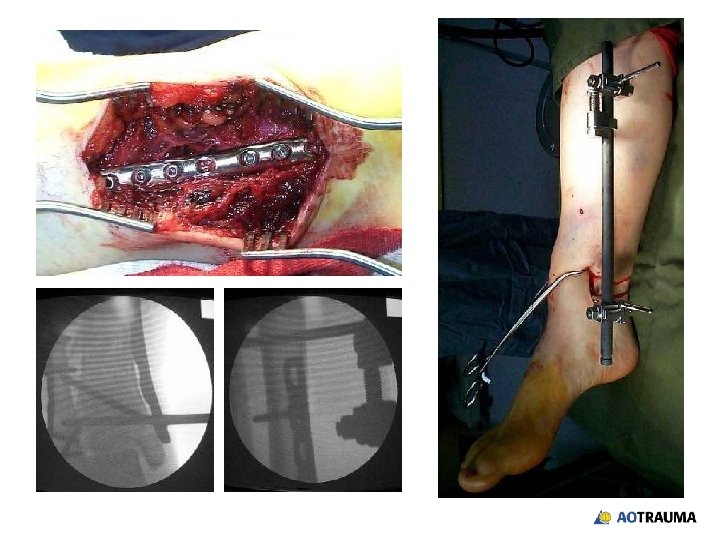

32 -year-old male, motor vehicle accident, open grade II

Reduction and fixation? 1. Closed indirect reduction and IM nailing 2. Closed indirect reduction and plate fixation 3. Closed indirect reduction and external fixation 4. Open direct reduction and plate fixation

Wound healed—what now? 1. Continue with external fixation 2. Closed reduction and retrograde nail 3. Closed reduction and locked plate 4. Open reduction and plating